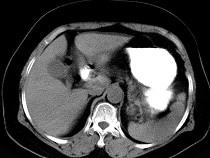

女43岁上腹不适多年,体检行CT扫描如图,最可能的诊断为()A.胃癌B.胃平滑肌瘤C.胃平滑肌肉瘤D.胃淋巴瘤E.胃蛔虫团块

问题 女43岁上腹不适多年,体检行CT扫描如图,最可能的诊断为()

选项 A.胃癌 B.胃平滑肌瘤 C.胃平滑肌肉瘤 D.胃淋巴瘤 E.胃蛔虫团块

答案 B